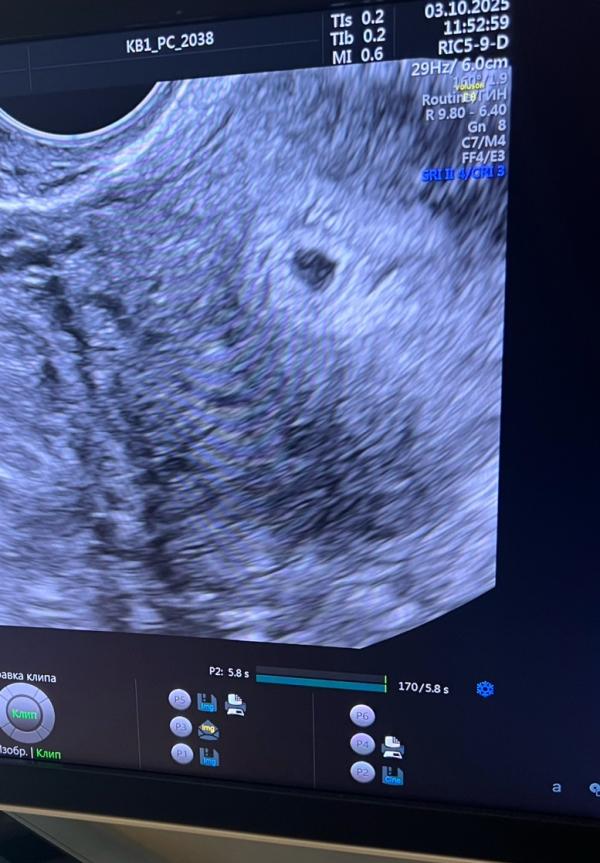

Плодное яйцо в матке 4,5 мм 🥳

Пожалуйста развивайся 🙏🙏 мы тебя очень ждём ♥️🥲